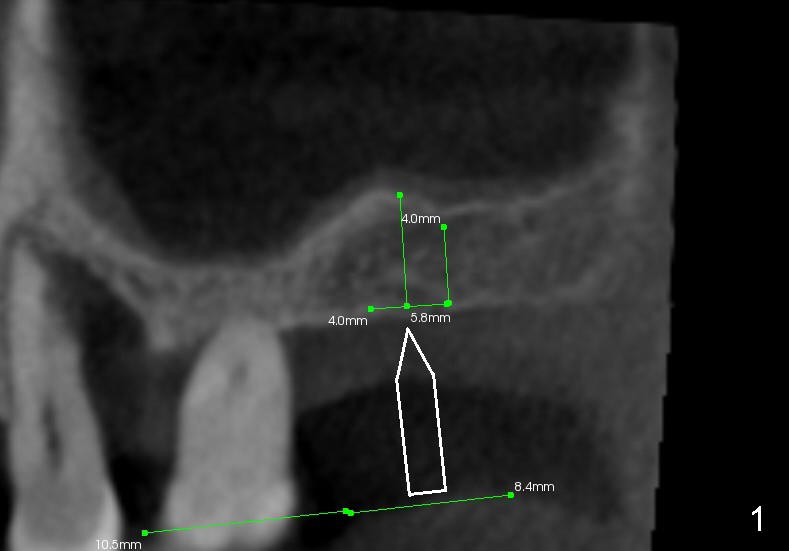

Fig.1 is a sagittal section of the posterior maxilla. A 2 mm (in diameter) round straight osteotome (white box) is going to initiate osteotomy and sinus lift. When the osteotome penetrates the bone initially, the latter is going to be condensed and pushed laterally (mesiodistally) and apically (Fig.2,3 arrows).

As the osteotome advances, some of the bone is brought apically (Fig.3 insert). The tapping with the thin osteotome should be stopped when penetration of the sinus floor is felt. The latter undergoes green stick fracture in a small area (Fig.4 arrows).